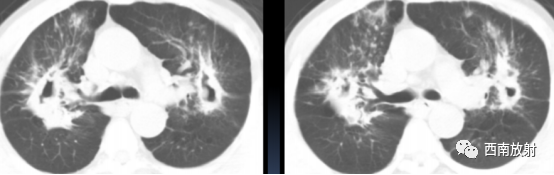

▲男,79 岁,脓肿分枝杆菌肺病,两肺多发支气管扩张伴小叶中心结节( 树芽征)

▲非结核分支杆菌肺病(龟-脓肿复合群分支杆菌)。